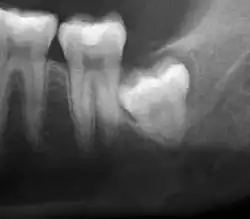

| Diagnostic method | Examination, x-ray |

If the tooth cannot be assessed with clinical exam alone, the diagnosis is made using either a panoramic radiograph or cone-beam CT. Where unerupted wisdom teeth still have eruption potential several predictors are used to determine the chance of the teeth becoming impacted. The ratio of space between the tooth crown length and the amount of space available, the angle of the teeth compared to the other teeth are the two most commonly used predictors, with the space ratio being the most accurate. Despite the capacity for movement into early adulthood, the likelihood that the tooth will become impacted can be predicted when the ratio of space available to the length of the crown of the tooth is under 1.[5]: 141